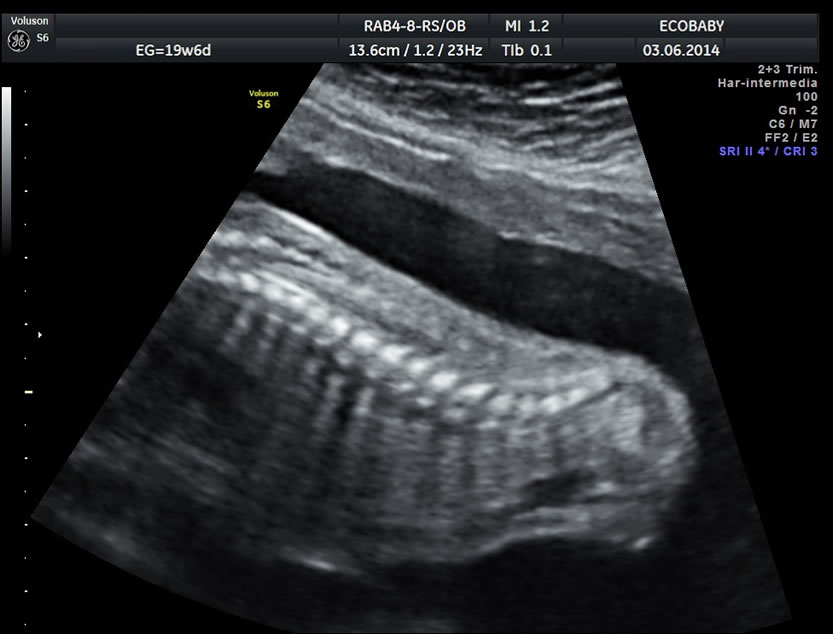

Se efectúa entre las semanas 20 y 24 aunque de ser necesario puede diferirse un poco. Más allá de las 30 semanas el tamaño del bebe y las sombras que ocasionan sus huesos impiden la visualización completa.

Cerebro, cuello, cara, tórax, corazón (diferentes cortes que muestran las cavidades y la correcta entrada y salida de arterias y venas), abdomen (normalidad de la pared, estómago, intestino, riñones, vejiga), miembros inferiores y superiores y columna vertebral.